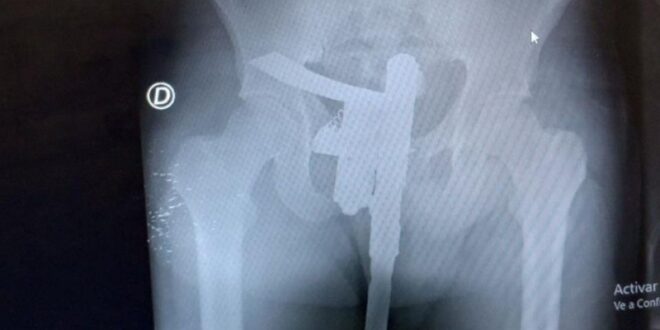

Un insólito hecho ocurrió en la mañana del domingo en el hospital José María Cullen de la ciudad de Santa Fe. Un enfermero que estaba de turno en el área de radiografías se sorprendió al descubrir en una placa que uno de los pacientes tenía un arma escondida entre sus ropas.

Se trataba de un joven de 25 años que había llegado al centro de salud producto de un accidente. Si bien no presentaba heridas de gravedad decidieron hacerle una placa para descartar lesiones internas.